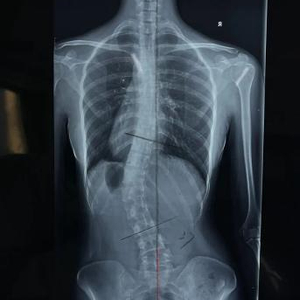

脊柱侧凸检查影像